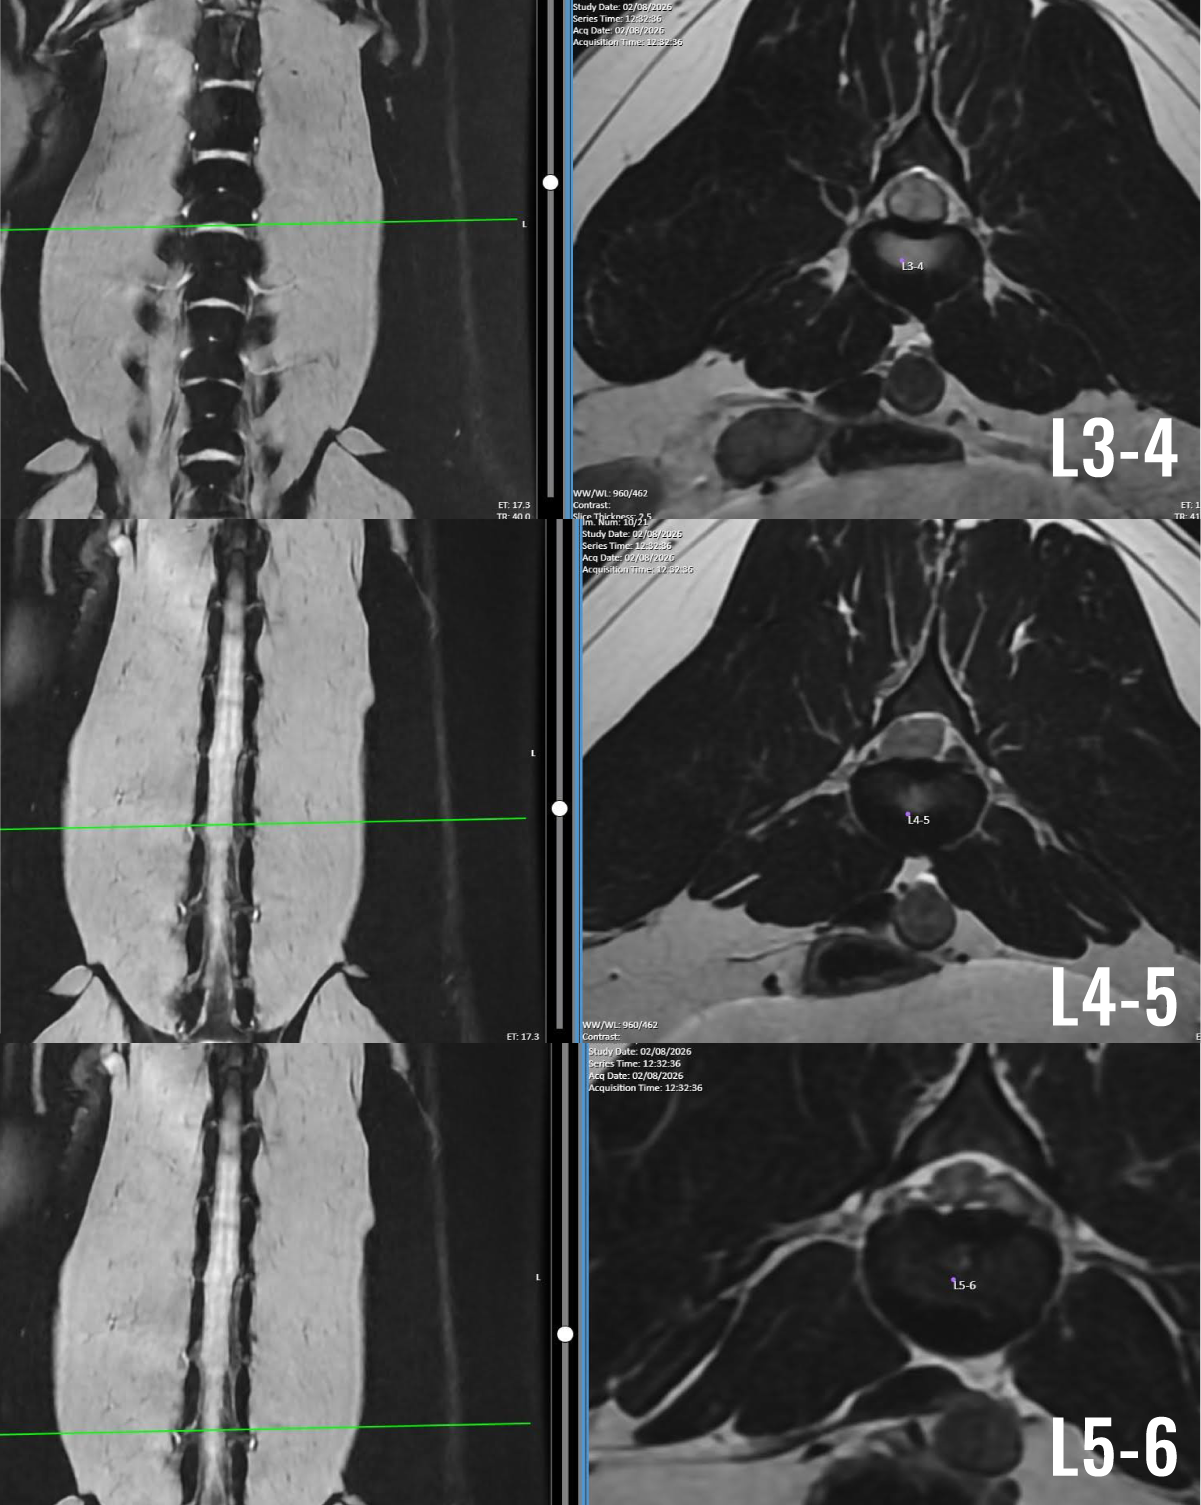

Misty’s MRI of her thoracolumbar spine revealed an extruded disc at L4-5 with a large amount of disk material spanning across her spinal cord from vertebrae L3-4 to L5-6. This material and the compression it caused on the spinal cord were responsible for the increasing weakness in Misty’s hindlimbs. It was clear that surgery was necessary and urgent.

MRI images show Misty’s spinal cord compression and disc material at each site (L3-4, L4-5, L5-6). These MRI images demonstrate severe spinal cord compression caused by extruded intervertebral disc material.